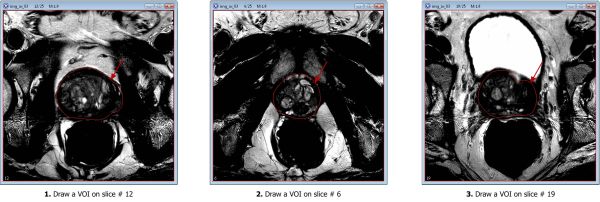

To delineate prostate VOIs, use the Polygon/Polyline VOI tool

from the MIPAV toolbar.

For example, if you work with the sample image dataset:

Smoothing VOIs. After delineating VOIs, we need to smooth each VOI. In order to do this, select each VOI and call the Smooth VOI dialog box. The dialog is available from the main MIPAV menu (VOI > Smooth VOI).

In the Smooth VOI dialog box, check the "Replace Original Contour" box, and set "Number of interpolation points" to 100. Click OK. Repeat for all 3 contours.